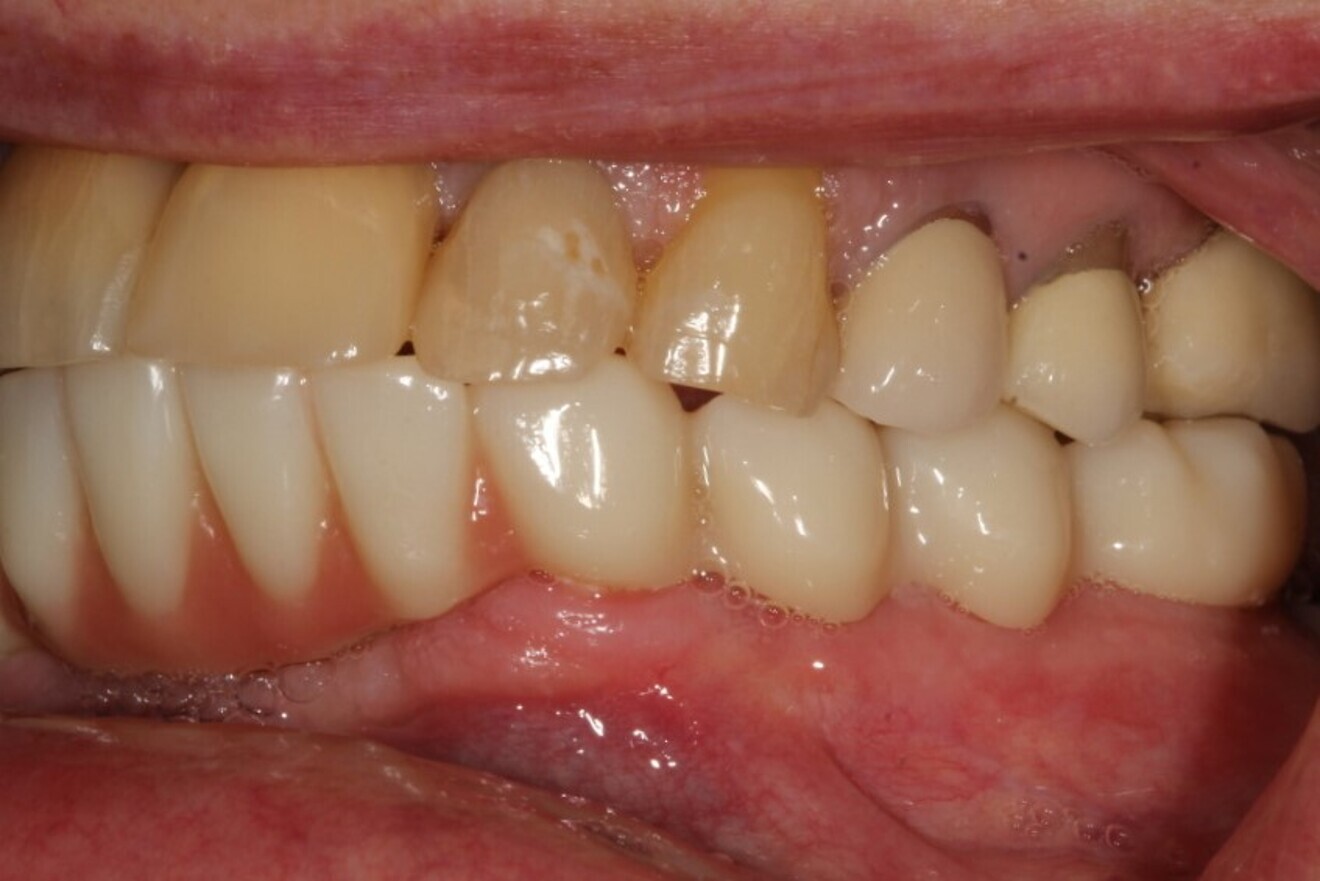

Figs. 18a & b: Final restoration in function.

A final full-arch zirconia restoration was manufactured, and the final seating was verified with radiographs (Fig. 17) and cemented with PANAVIA SA Cement Universal (Kuraray Noritake Dental). The patient returned two weeks later for an occlusion check and adjustment along with an oral hygiene check. Pink firm gingiva around all the implants was noted such that it was even difficult to get a probe into the sulcus (Fig. 18).